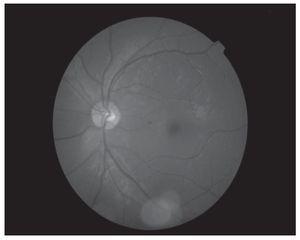

Hombre de 13 años de edad, sin antecedentes heredofamiliares ni personales patológicos de importancia. El motivo de consulta fue la disminución progresiva de la agudeza visual de meses de evolución, acompañado en ocasiones de dolor periocular intermitente. A la exploración física se encontró una talla de 1.52 m, la cual se encuentra dentro de la percentila 50 para la edad, así como una discreta braquidactilia en ambas manos. La exploración oftalmológica reveló: agudeza visual de 20/400 en ambos ojos y una agudeza visual mejor corregida de 20/30 y 20/40 respectivamente, con una refracción de -11.00 = -0.75X145° en OD y -11.00 = -2.50X5° en OI. La posición primaria de la mirada en ortoposición y los movimientos oculares fueron normales. La presión intraocular fue de 26 mmHg en OD y 21 mmHg en OI. El segmento anterior de ambos ojos bajo lámpara de hendidura, mostró una cámara anterior estrecha, tanto en la periferia como en el centro (Figuras 1a y 1b) con un ángulo iridocorneal en ambos ojos de 0 en los 360° (Figuras 2a y 2b). En segmento posterior de ambos ojos encontramos una excavación papilar de aproximadamente 6/10, con un defecto en la capa de fibras nerviosas evidenciada por las fotografías libres de rojo (Figuras 3a y 3b). El paciente fue tratado inicialmente mediante la realización de iridotomías con láser de YAG en ambos ojos y tratamiento tópico con una combinación brimonidina-timolol-dorzolamida, acudiendo nuevamente a consulta dos días posteriores al tratamiento encontrando una presión de 13 mmHg en ambos ojos con las iridotomías permeables (Figura 4).

¿ Figura 3a. OD. Polo posterior. Defecto en capa de fibras nerviosas.